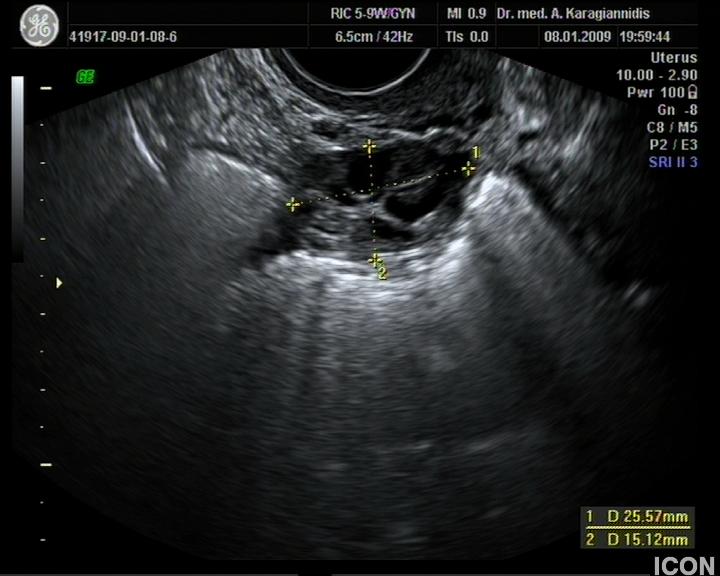

Ενδοκολπικός U/S έσω Γεννητικών Οργάνων